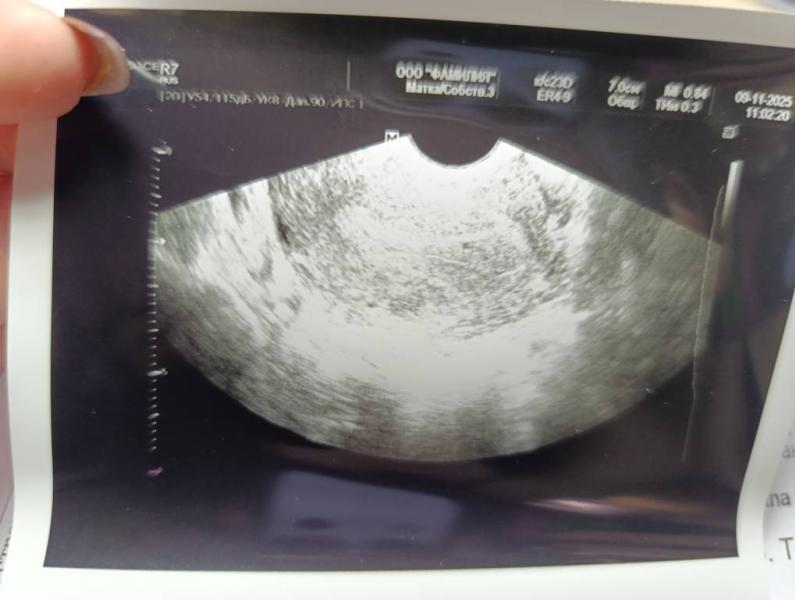

Девочки, было ли у кого-то такое, чтобы в 5-6 недель не было видно плодного яйца? Сегодня ровно 6 недель, но допускаю, что может быть чуть меньше где-то 5 с копейками. На УЗИ пусто. Прикрепляю два УЗИ с разницей в неделю. Может ли быть шанс, что ещё не всё потеряно?

@6565a плодного яйца не видно, есть какая-то точка 2.5мм, сказали что вероятнее всего это оно и остановилось на очень раннем сроке